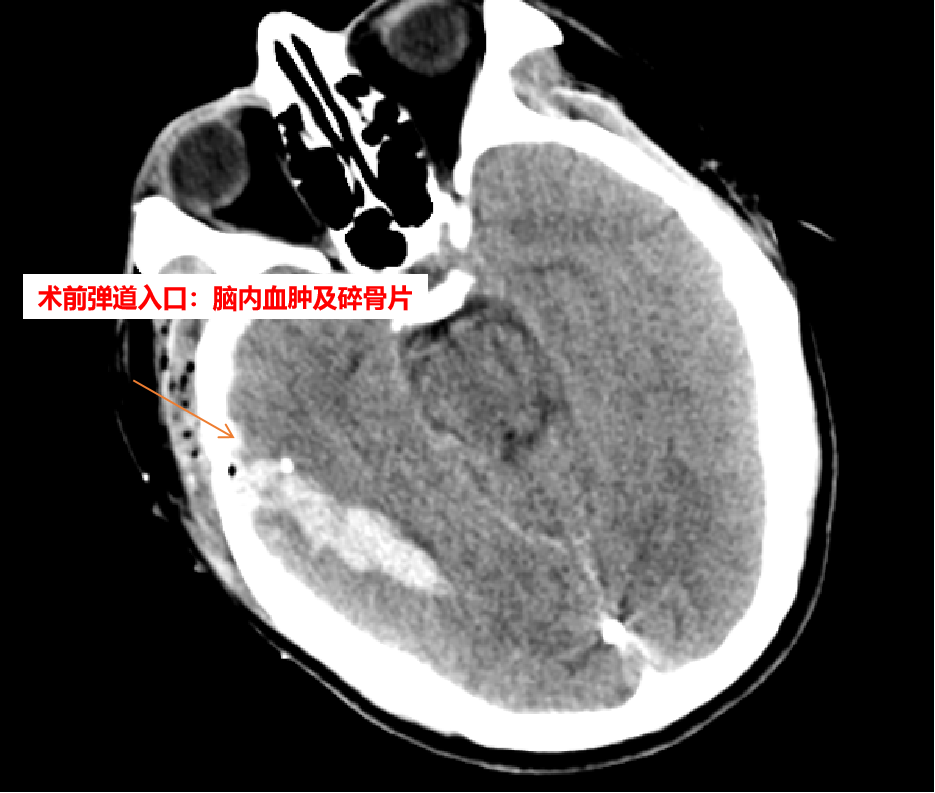

患者张某平,男,41岁,因“重型颅脑爆炸伤”于2021年10月10日收入兰陵县人民医院颅脑创伤外科进行抢救。一颗子弹自患者右侧颞部击碎颅骨进入脑内约15cm,造成多个颅骨碎骨片进入脑内,并造成弹道内的峰脑内血肿,医护人员在充分术前准备下立即行开颅血肿清除异物和脑内血肿手术。

术中见右颞骨一0.5*0.5cm大小的洞口,用铣刀做出约10*6cm大小骨瓣,取下骨瓣后见右颞叶表层一1*1cm大小洞口,沿洞口进入,清除多枚碎骨片及脑内血肿,并仔细止血,放置引流管一枚,术毕回病房。